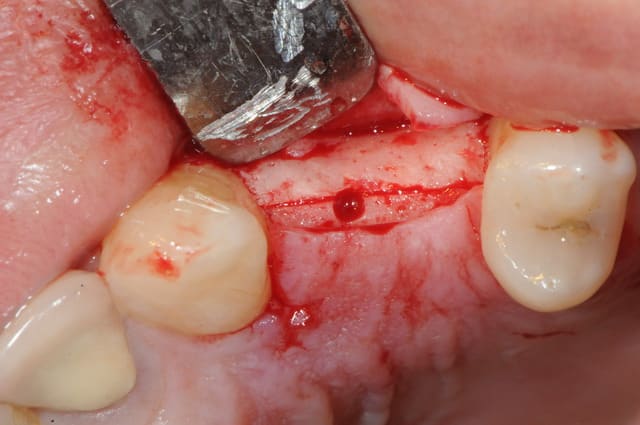

je me permet d'apporter un maigre contribution à ce poste.

mais avant, tout un petit historique du cas...

il y a 15 jours donc.

1 : 24 abscente et 25 distalé

2: mise en évidence de l'espace trop important

Plan de traitement: pose implant 24 puis utilisation de cet implant comme ancrage absolu pour mésialer 25.

3 : vu de dessus/dessous

4 : incision crestale - lambeau de pleine épaisseur

5 : incision de la corticale osseuse avec disque diamanté Komet

6 : bone spliting (pas top, je l'avoue) avec ciseaux à os (aesculap je crois)

(je donne la marque , mais je touche rien!!! c'est juste pour info)

7 : système D pour ceux qui pas équipé de Tatum, un simple décolleur de Molt

8 : pose implant

9 + 10: vital os et sutures.